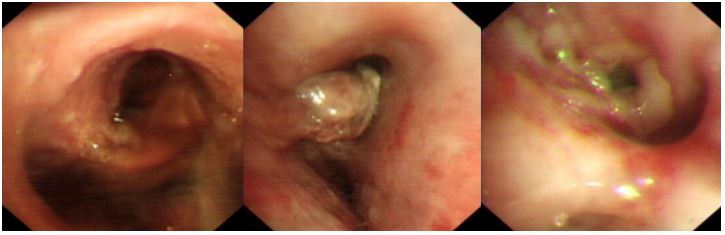

患者10余天前出现咯血,于当地医院接受了抗感染、止血等治疗,治疗后咯血好转。胸部CT(2021-05-14,外院):两肺炎症,散在纤维条索影(图1)。5月17日气管镜提示左肺下舌段管口可见肉芽增生,活检后明显出血(图2)【活检组织并未送病理】,量约500 ml,SpO2降至65%。立即予止血、吸氧等治疗,咯血量减少。但患者仍反复咯血,5月17日转入ICU,予有创机械通气、止血治疗。

图片

图1  患者外院胸部CT(2021-05-14)

图2  患者支气管镜检查(2021-05-17)